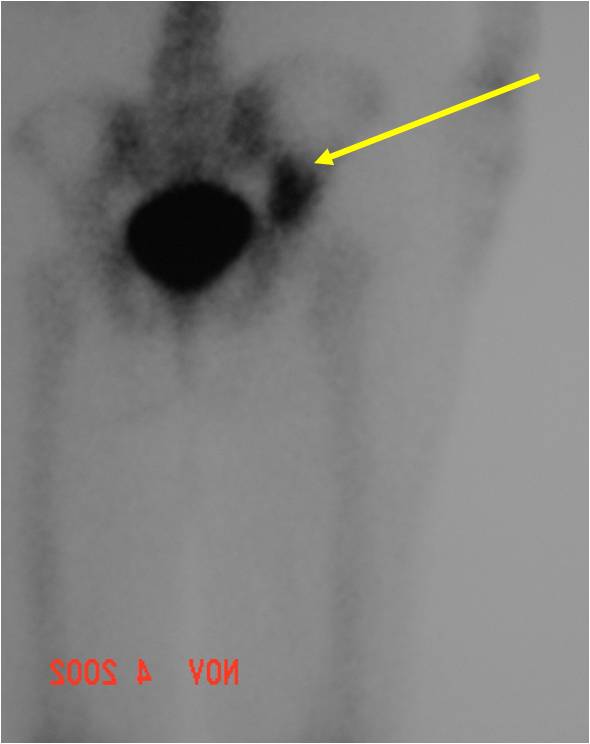

Biological Behavior

- Very aggressive locally

- Frequently cortical perforation

- Mass is usually large if extraosseous extension occurs

- Extremely high metastatic rate

- Metastasizes primarily to lungs

- Also bones and other organs